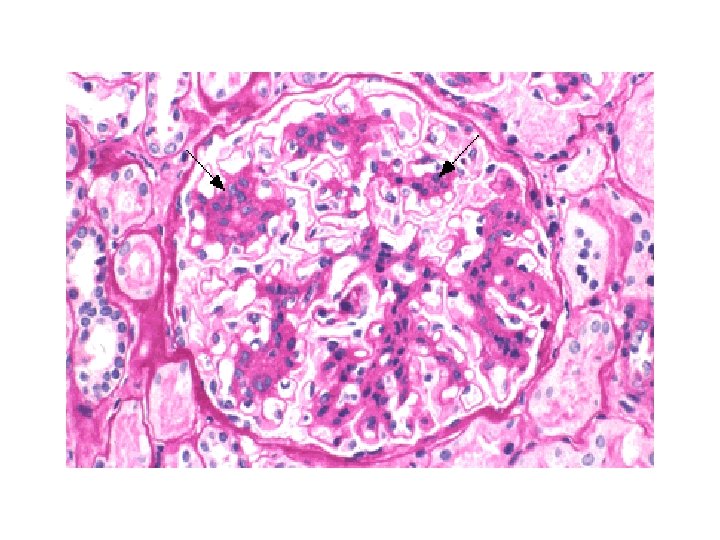

Ig. A nephropathy • Aetiology • - commonest GN on renal biopsy, more common among japanese than europeans and can also run in families though mode of inheritance unclear • Presentation • - usually with micro or macro haematuria esp following URTI, but also with asymptomatic proteinuria, nephrotic syndrome (3%), CRF and occas as RPGN with crescentic nephritis • Diagnosis • - biopsy shows mesangial proliferation with deposition of Ig. A. identical to HSP (not HUS which shows intraglomerular thrombi) • Treatment • - control of HT, otherwise no specific therapy has been shown to alter progression to ESRD. No evidence that tonsillectomy helps • Outcome • - 10 -30% progress to ESRD over 20 years (the commonest primary GN leading to renal failure)

Ig. A nephropathy • Aetiology • - commonest GN on renal biopsy, more common among japanese than europeans and can also run in families though mode of inheritance unclear • Presentation • - usually with micro or macro haematuria esp following URTI, but also with asymptomatic proteinuria, nephrotic syndrome (3%), CRF and occas as RPGN with crescentic nephritis • Diagnosis • - biopsy shows mesangial proliferation with deposition of Ig. A. identical to HSP (not HUS which shows intraglomerular thrombi) • Treatment • - control of HT, otherwise no specific therapy has been shown to alter progression to ESRD. No evidence that tonsillectomy helps • Outcome • - 10 -30% progress to ESRD over 20 years (the commonest primary GN leading to renal failure)

Renal Immunofluorescence and Electron Microscopy • Ig. A nephropathy - mesangial deposition of Ig. A • Lupus - full house IF of Ig. G, Ig. A, Ig. M, C 3, C 4 • Membranous - granular staining for Ig. G along GBM with subepithelial immune complex deposits “spikes” on silver staining • Minimal change - foot process fusion on EM only • AASV - no immunoglobulin deposition - described as pauci immune to distinguish from lupus in patient with crescentic nephritis

Renal Immunofluorescence and Electron Microscopy • Ig. A nephropathy - mesangial deposition of Ig. A • Lupus - full house IF of Ig. G, Ig. A, Ig. M, C 3, C 4 • Membranous - granular staining for Ig. G along GBM with subepithelial immune complex deposits “spikes” on silver staining • Minimal change - foot process fusion on EM only • AASV - no immunoglobulin deposition - described as pauci immune to distinguish from lupus in patient with crescentic nephritis